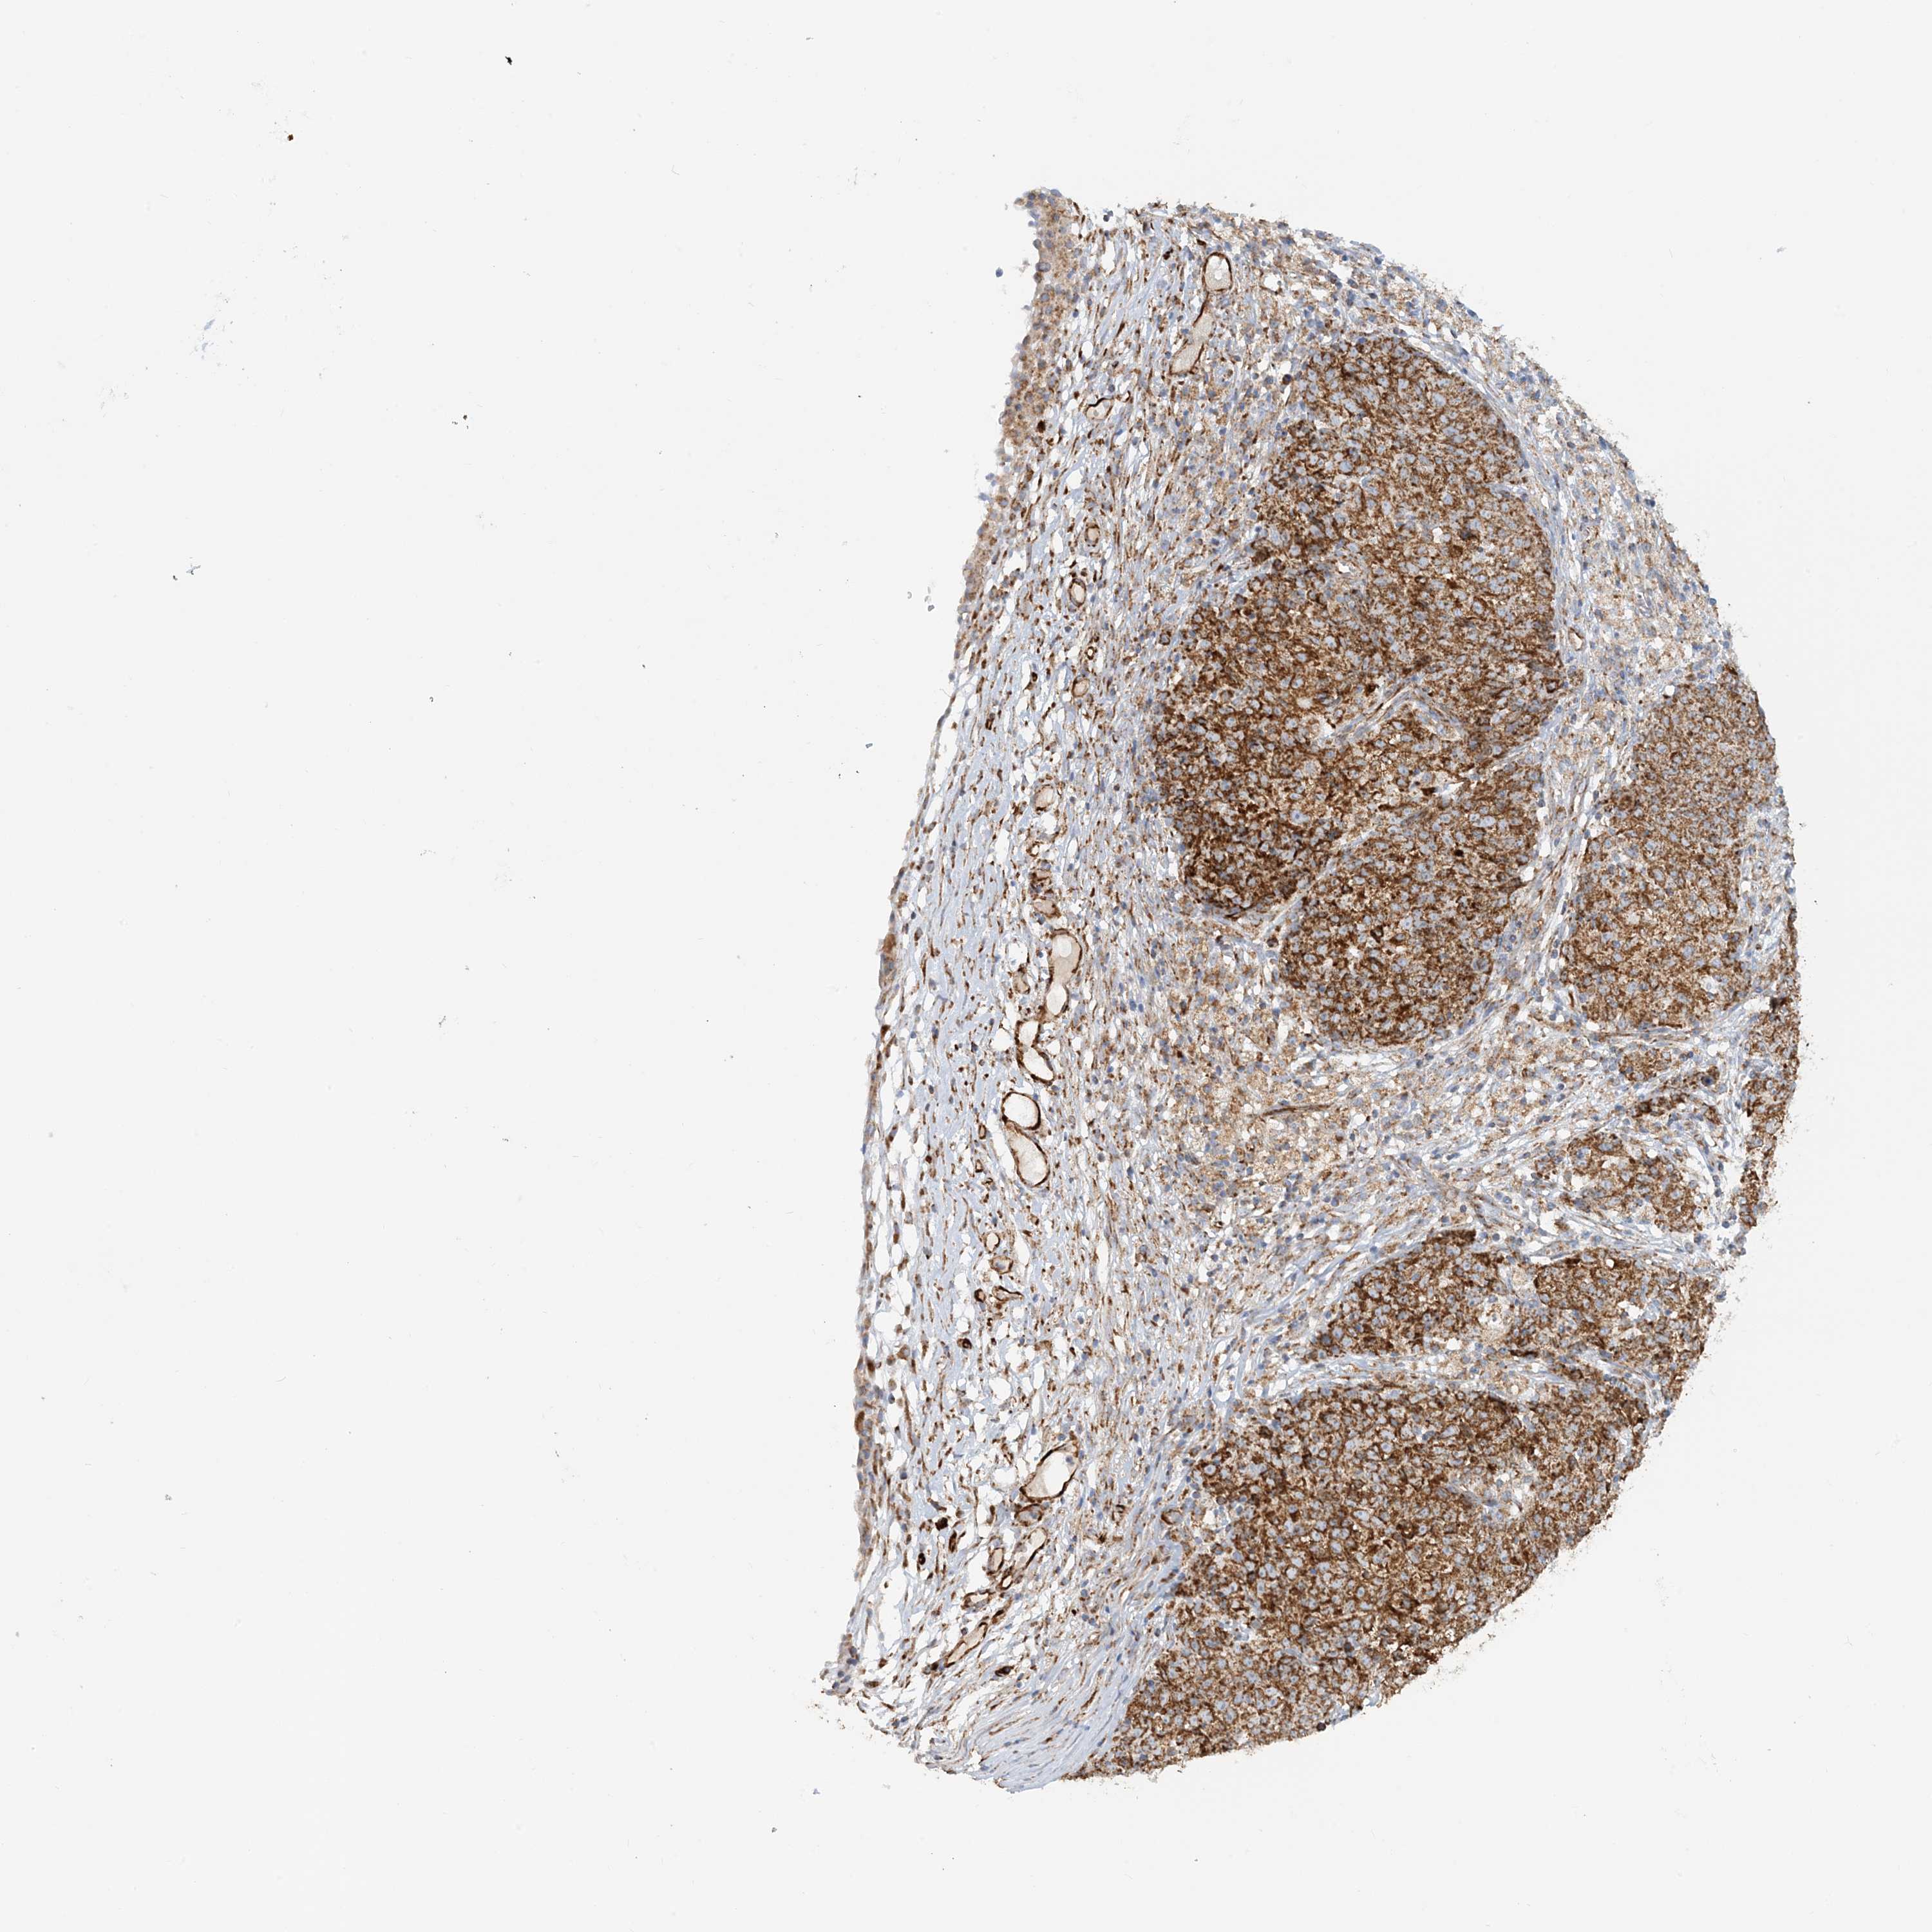

OVARIAN CANCER - Protein expressioni

A mouse-over function shows sample information and annotation data. Click on an image to view it in a full screen mode. Samples can be filtered based on level of antibody staining by selecting one or several of the following categories: high, medium, low and not detected. The assay and annotation is described here.

Note that samples used for immunohistochemistry by the Human Protein Atlas do not correspond to samples in the TCGA dataset.

Antibody stainingi

Antibody staining in the annotated cell types in the current human tissue is reported as not detected, low, medium, or high, based on conventional immunohistochemistry profiling in selected tissues. This score is based on the combination of the staining intensity and fraction of stained cells.

Each image is clickable and will lead to virtual microscopy that enables deeper exploration of all samples and also displays staining intensity scores, fraction scores and subcellular localization as well as patient and tissue information for each sample.

Antibody HPA031966

Cystadenocarcinoma, serous, NOS

Carcinoma, endometroid

Cystadenocarcinoma, mucinous, NOS

Carcinoma, NOS